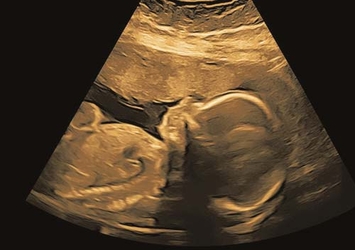

ab 12+5 Wochen; inklusive Nackenfaltenmessung, Nasenbein, Ductus venosus u.v.m.

fetale Echokardiographie

frühe fetale Neurosonographie

fetale Echokardiographie, optimal zwischen 20.–22. Woche

detaillierte Untersuchung von Gehirn und Rückenmark

3D / 4D-Ultraschall